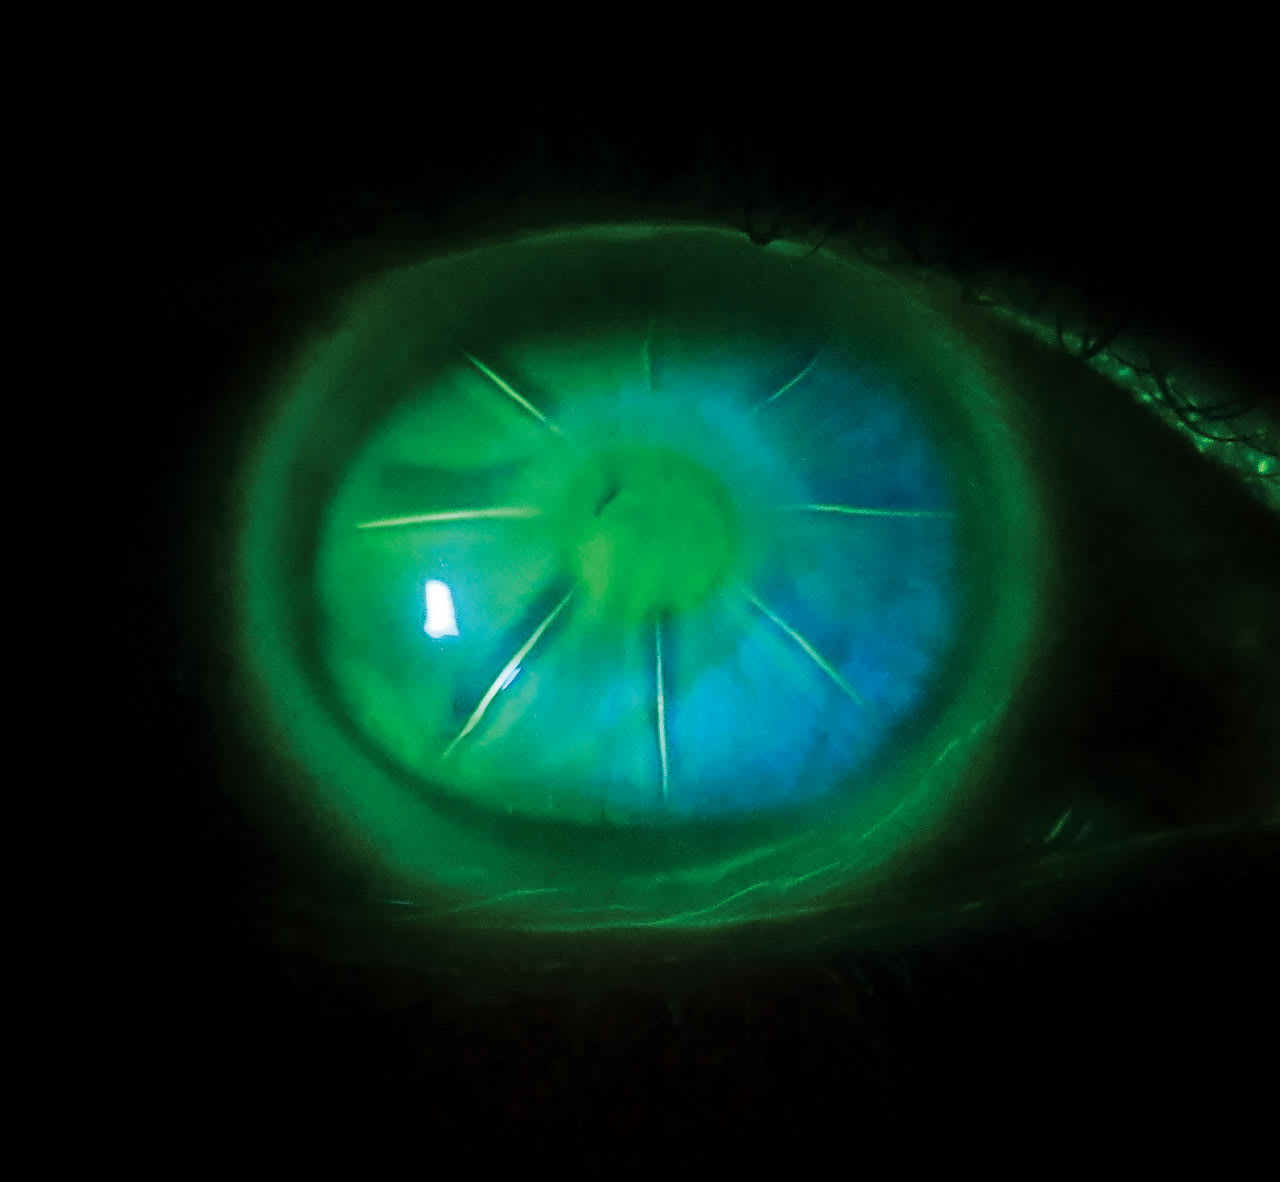

ALTHOUGH RADIAL keratotomy (RK) was eventually eclipsed by laser vision correction, 250,000 RK procedures were performed annually at the peak of its popularity in the early 1990s for the correction of myopia (National Eye Institute, 1994). The surgery involved making 4 to 32 (sometimes more!) deep radial corneal incision (Figures 1 and 2) that resulted in corneal flattening. Three-year results of the Prospective Evaluation of Radial Keratotomy (PERK) study showed that 58% of eyes had refractive error within 1.00 D of emmetropia, 26% were undercorrected, and 16% were overcorrected by more than 1.00 D (Waring et al, 1987).

Slit lamp examination showed 8-incision RK in each eye, without additional scarring or neovascularization. The patient habitually wears scleral lenses that provide her stable vision without any diurnal fluctuations. The lenses had parameters of 16.5 mm diameter, base curve (BC) of 37.5 D (sag 4525 µm), and toric landing zone 241 µm, +2.25 20/20 OD; and 16.0 mm diameter, BC of 41.75 D (sag 4318 µm), and toric landing zone 196 microns, –3.37 20/25 OS. The Dk of the lens material was 180.